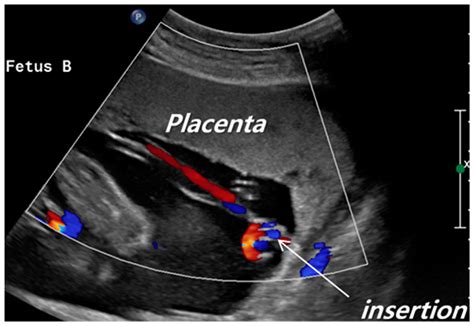

Velamentous Cord Insertion Ultrasound

Discover essential facts about marginal cord insertion, a pregnancy condition where the umbilical cord attaches to the placenta's edge. Learn about potential risks, diagnostic ultrasound methods, and management strategies for expectant mothers. Understand how this placental variation impacts fetal development and birth outcomes to ensure a healthy, well-informed pregnancy journey.